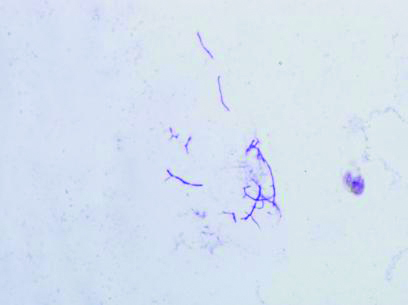

| 图 3 胸水标本表现出分歧杆菌革兰染色阳性提示奴卡菌感染(1 000×) |

| 图 4 抗酸染色见不典型分歧杆菌 |